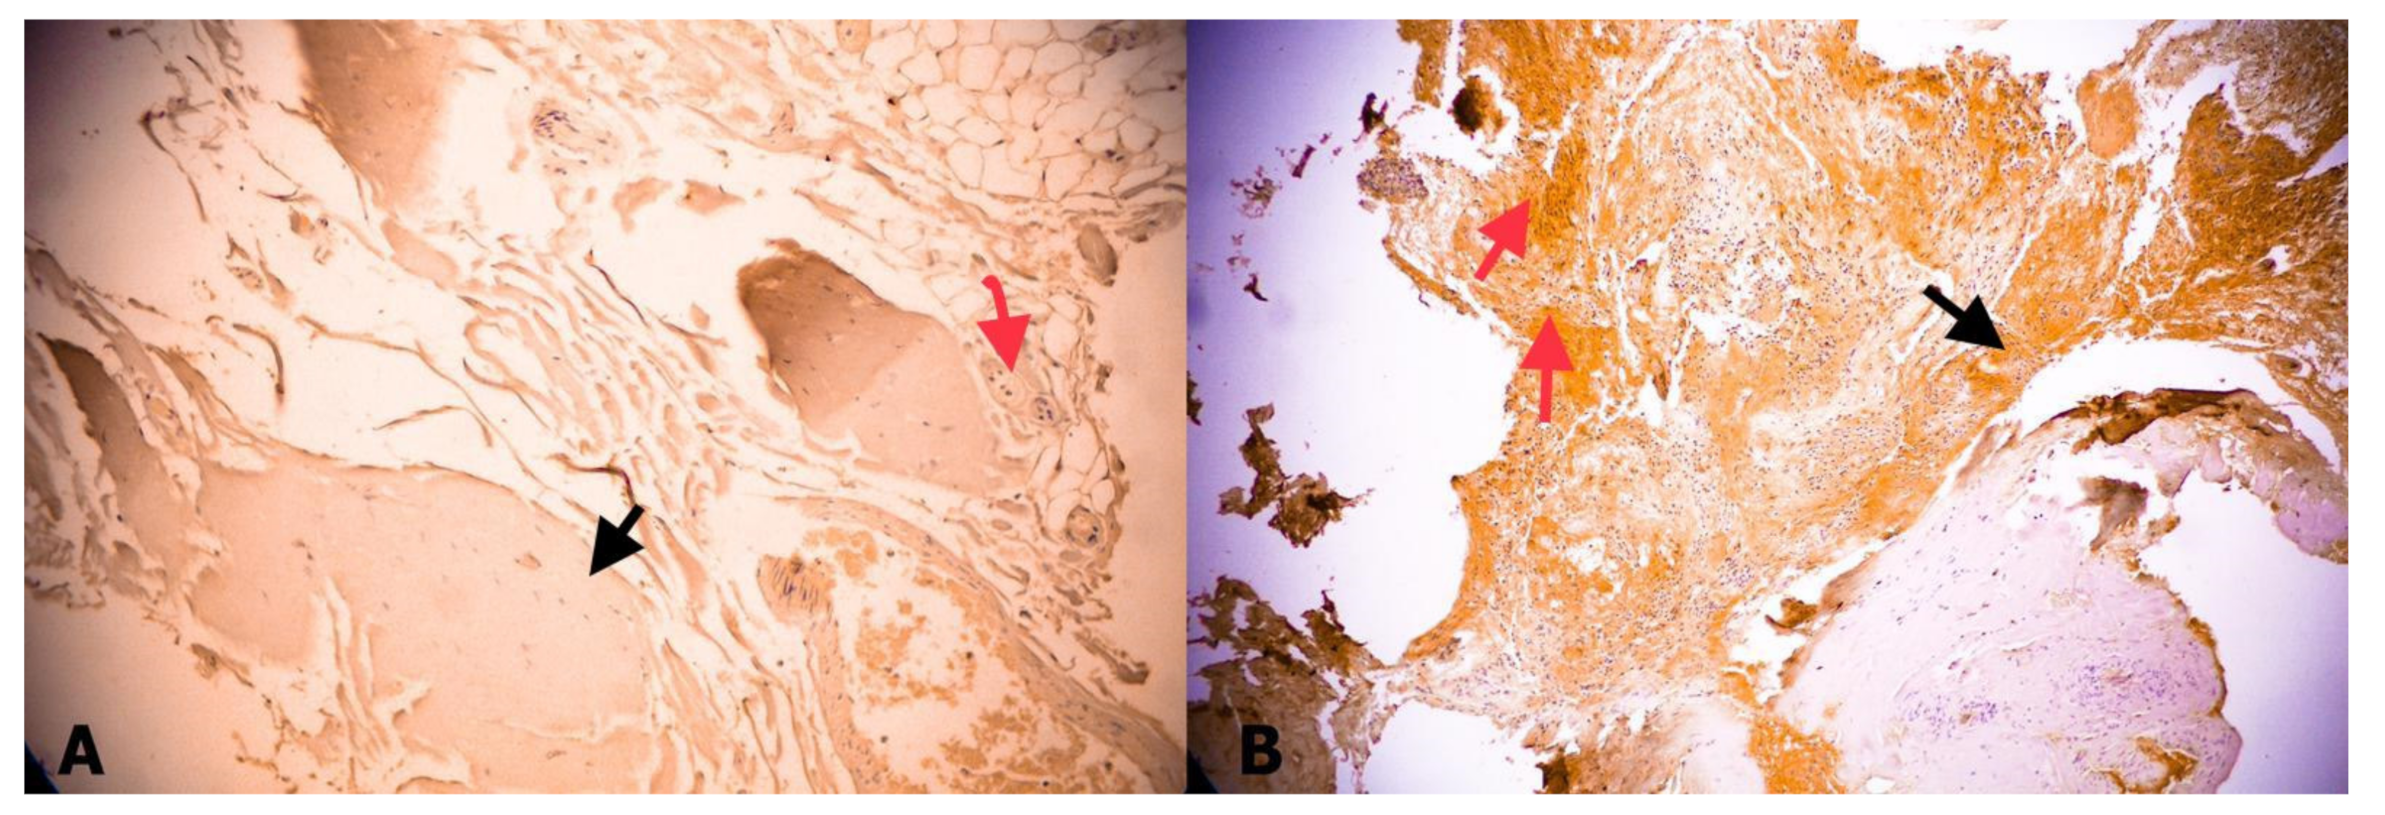

- Tehli, O.; Hodaj, I.; Kural, C.; Solmaz, I.; Onguru, O.; Izci, Y. A comparative study of histopathological analysis of filum terminale in patients with tethered cord syndrome and in normal human fetuses. Pediatr. Neurosurg. 2011, 47, 412–416. [Google Scholar] [CrossRef]

- Kural, C.; Guresci, S.; Simsek, G.G.; Arslan, E.; Tehli, O.; Solmaz, I.; Izci, Y. Histological structure of filum terminale in human fetuses. J. Neurosurg. Pediatr. 2014, 13, 362–367. [Google Scholar] [CrossRef]

- Hendson, G.; Dunham, C.; Steinbok, P. Histopathology of the filum terminale in children with and without tethered cord syndrome with attention to the elastic tissue within the filum. Childs Nerv. Syst. 2016, 32, 1683–1692. [Google Scholar] [CrossRef] [PubMed]